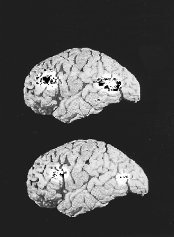

Синаптическая щель между двумя мозговыми клетками (снимок сделан под микроскопом). Видно скопление гормонов (белые точки), которые биохимическим путем передают сигналы от одной клетки к другой и таким образом направляют реакцию организма.

РАБОТА СИНАПТИЧЕСКОЙ ЩЕЛИ

Сообщение между клетками мозга - нейронами - происходит через так называемую синаптическую щель, то есть через пространство, разделяющее мембраны клеток, находящихся в контакте. Приоткрытая клетка выделяет носитель информации, например серотонин. Этот переносчик сообщений осаждается на специфических рецепторах другой клетки. Сигналы, полученные рецепторами, воздействуют на нейрон и активизируют его. За этим следует защитная реакция организма.